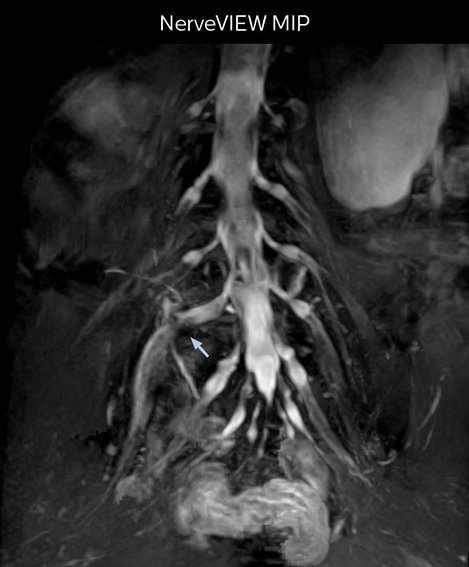

“In patients with lower extremity neurological symptoms, NerveVIEW helps us to determine the disease matching the patient’s symptoms by directly visualizing the nerves. We use the sequence mainly, when there is suspicion of intraforaminal stenosis, extraforaminal stenosis or lateral disc herniation, which is often based on routine T2- and T1-weighted images. Additionally, the excellent depiction of the course of nerves makes NerveVIEW a good navigator when applying treatment such as block therapy or surgery.”

The key concept in MR neurography, Dr. Yabuki stresses, is the ability to directly visualize spinal nerves, versus inferring the presence of pathology indirectly. “Before NerveVIEW, we estimated compression of the nerve by looking for the presence or absence of fat signal on other MR images,” he says.

“For example, in sagittal images, when the presence of fat is observed in the intervertebral foramen, it suggests that there is a margin around the nerve. Similarly, the absence of fat indicates that the nerve is being compressed. So, we used to deduce nerve compression indirectly. With NerveVIEW, however, we can observe the condition of the nerves directly, regardless of the presence or absence of fat. We always prefer such direct observation of anatomy over having to make an inference about it.”

Distinguishing typical from atypical herniation informs the surgeon

“NerveVIEW is really useful for those cases where a nerve disorder is strongly suspected based on the clinical examination but our regular MRI images do not show any findings. These atypical herniations and spinal canal stenosis, occurring in 5% to 15% of the total lumbar herniation/stenosis cases are our main target when using NerveVIEW,” says Dr. Yabuki.

“Although symptoms of typical disc herniation and atypical hernia are very similar, the actual site of herniation is different. It is therefore important to characterize the nerve’s condition both inside and outside of the intervertebral foramina.

Because the obtained NerveVIEW images often exhibit a high signal in the intervertebral discs, we use partial MIP images to eliminate such intervertebral disc high signals. MIP image generation is based on the  center of the coronal stack, and RAO (right anterior oblique) and LAO (left anterior oblique) images rotated in the range of 45 degrees are used for diagnosis.